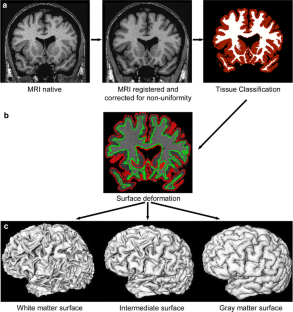

Brain imaging research with MRI spans a wide area, covering both structure and function, and ranging from basic research through clinical research to drug design and clinical trials. In recent years there has been a trend towards the collection of very large MRI databases which can allow for the detection of very small group-dependent effects. However, the logistical challenges of analysing such large datasets presents new challenges. This paper describes the “pipeline” framework developed at the Montreal Neurological Institute for the fully automated morphometric analysis of large brain imaging databases. The potential use of these techniques is illustrated by examples of their applications in multiple sclerosis, Alzheimer’s disease, and pediatric development.

Fig. 2